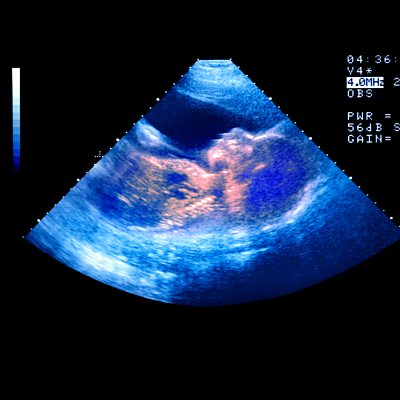

You and Yours reveals the latest Instagram fraud, which involves not only scamming you out of your money, but hijacking your account in order to scam your family and friends. We hear from a woman who sent £1200 to scammers, and lost control of her phone and Instagram account. A growing number of women are paying for private scans during their pregnancy. In Which's survey last year of 1000 parents-to-be, 30% had paid for a private scan. Typical reasons are for reassurance, to get a clearer photo or to find out the sex. However there are concerns that medical issues are sometimes being missed. We hear from Kate Richardson from The Birth Company in Harley Street London, and Dr Daghni Rajasingam, consultant obstetrician and spokesperson for the Royal College of Obstetricians and Gynaecologists. Have you paid for a scan while pregnant? Let us know youandyours@bbc.co.uk And Ugg Boots are back! We hear about the latest 'Y2K' trend that's back in fashion. Presenter: Shari Vahl Producer: Miriam Williamson